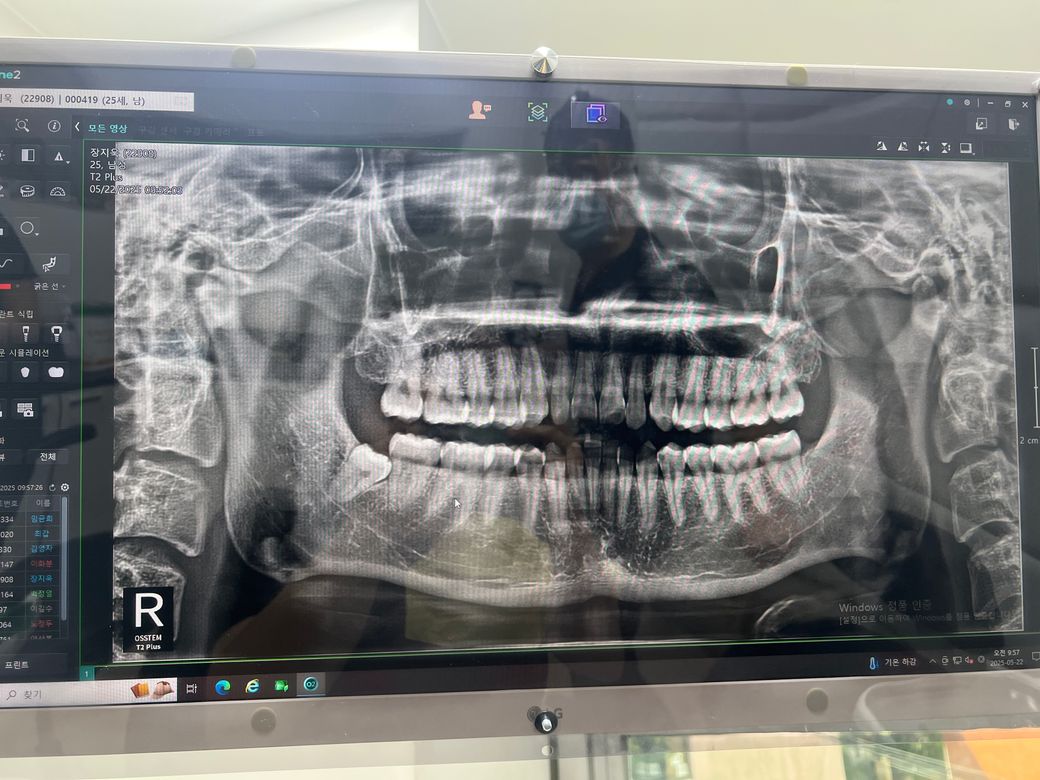

엑스레이에서 보이는 거처럼 사진에선 왼쪽아래 제기준 오른쪽 아래 매복 사랑니를 뽑았는데 뭔가 주변 치아도 밀리는 느낌이 나고 휴지로 갖다 대보면 노란 액체도 묻어나와서 염증도 있는거 같아요 혹시 치과에서 처치를 잘못한 상황일 수 있을까요?

• 1번 째 사진